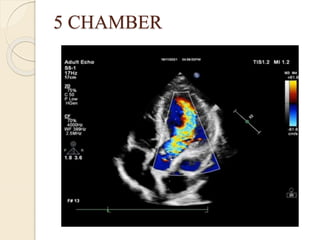

5 CHAMBER

• Apical five chamber view